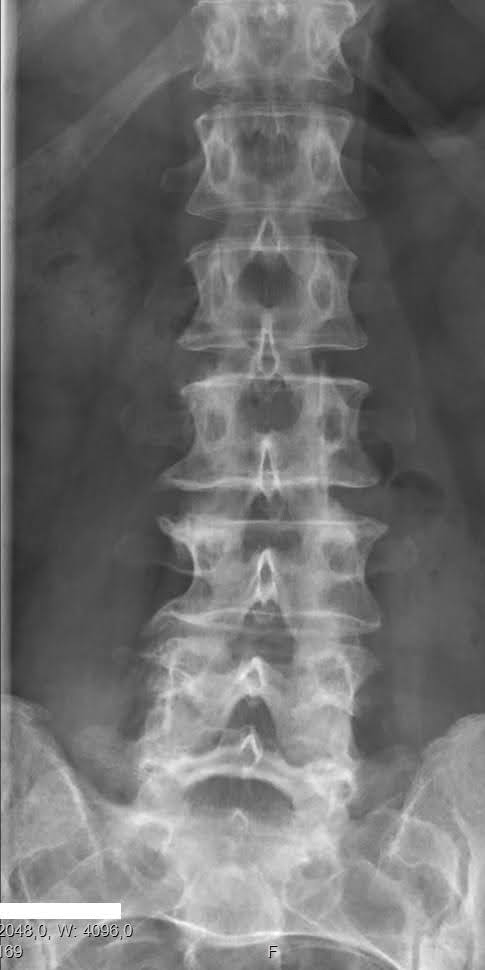

Name of condition seen in these images

https://photos.app.goo.gl/4TzEWbHzctdffqT1A

What is a lumbarization of S1?